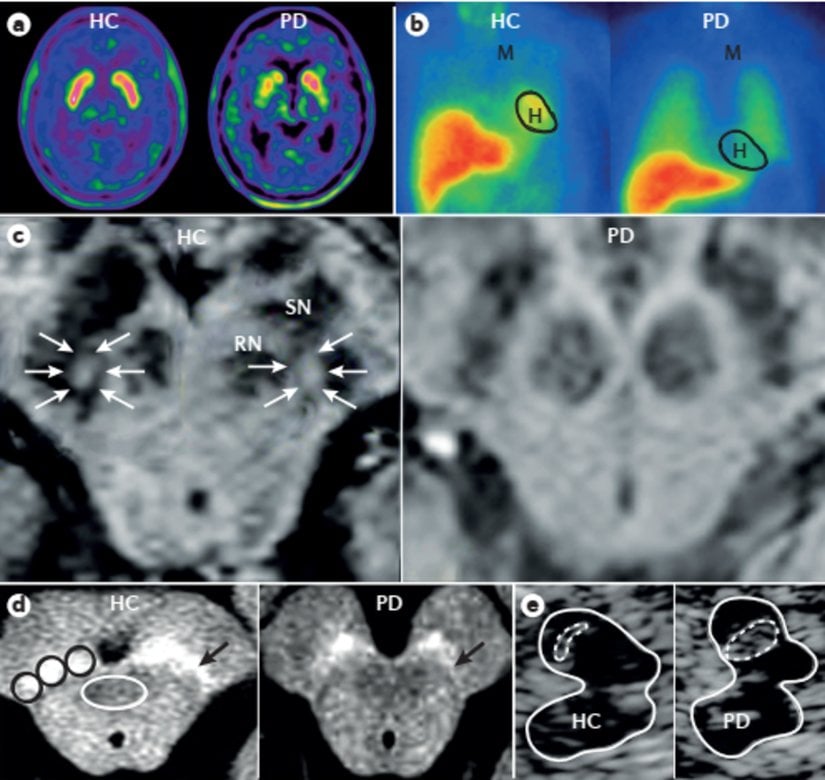

Parkinson hastalığı olan hastalarda striatal dopamin tükenmesinin 18F etiketli l-DOPA ve PET kullanılarak görselleştirilmesi, 1980'lerin başında moleküler nörogörüntülemede bir dönüm noktasıydı. O zamandan beri, nörogörüntüleme alanında, Parkinson hastalığıyla giderek daha alakalı hale gelen yenilikçi ilerlemeler görüldü. Örneğin, 123I ioflupane tek foton emisyonlu CT, (SPECT) (DaTscan (GE Healthcare) olarak da bilinir) klinik rutin kullanım için onaylanmıştır ve Parkinson hastalığı ile presinaptik nigrostriatal terminal disfonksiyonu ile ilişkili olmayan klinik mimikleri (Hastalık ile aynı belirtilerin ortaya çıkmasına sebep olan klinik fizyolojik durumlar) ayırt etmek için kullanılabilir.

Yapısal MRI semptomatik parkinsonizmi tanımlamaya yardımcı olur ve çeşitli MRI teknikleri, atipik parkinsonizmde bazal ganglionlarda ve infratentoryal yapılarda spesifik değişiklikleri ortaya çıkarabilir. Difüzyon ağırlıklı görüntüleme, volümetrik görüntüleme, otomatik subkortikal hacim segmentasyonu ve multimodal görüntüleme dahil olmak üzere gelişmiş MRI teknikleri ve işlem sonrası prosedürler, diğer dejeneratif parkinsonizm türlerine karşı Parkinson hastalığının tanısal doğruluğunu artırmak için araştırılmaktadır. Noradrenerjik izleyiciler kullanılarak PET veya SPECT ile değerlendirilen miyokardiyal sempatik denervasyon, Parkinson hastalığında yaygındır, ancak atipik parkinsonizm veya diğer Parkinson hastalığı taklitleri olan hastalarda görülmez.